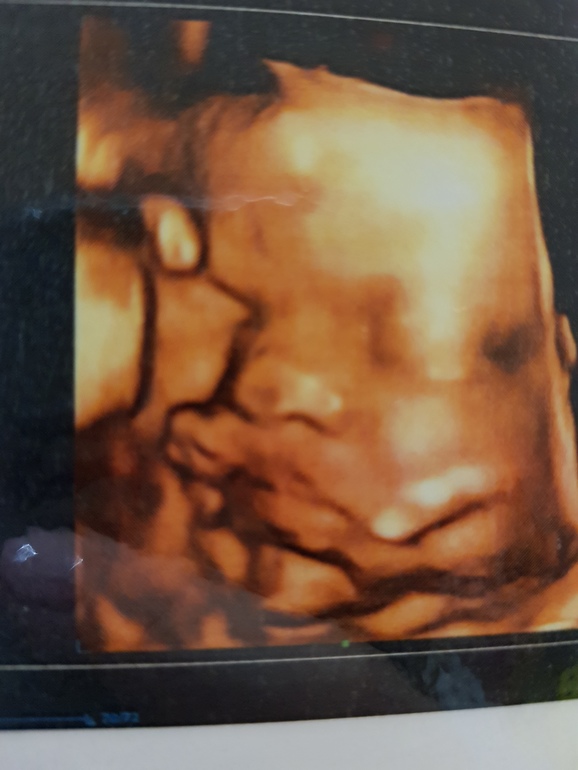

УЗИ 30 недель

Любопытно, узи так искажает размеры носика и губ или все таки они на столько огромные))) Наша малышка в 30 недель, уже на фото судя по двум пальцам у нее все отлично!😍